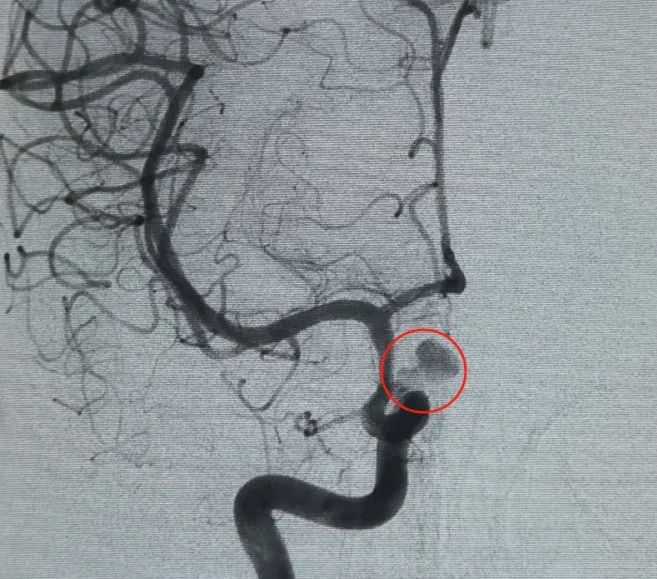

Diagnostic: Anévrisme de l'artère ophtalmique du segment C6 de l'artère carotide interne gauche

Un Perfiller®Bobine expansible de 3mm × 6 cm et un Perfiller®Une bobine expansible de 3mm x 2 cm a ensuite été placée pour compléter l'occlusion du cou. Par la suite, une Nuva®Le déviateur d'écoulement (TJED-D-5.0-16) a été livré et déployé à travers le col de l'anévrisme. L'angiographie de suivi dans les vues antéropostérieures et latérales a confirmé une excellente couverture, une bonne apposition de la paroi et une radiopacité claire, avec une stagnation marquée du contraste.